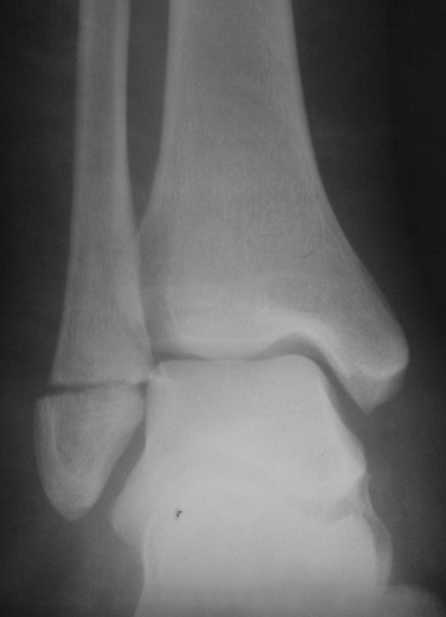

На одном из форумов заспорили о тактике.Женщина 23 года, рост 158, вес 55, профессия: менеджер, хобби: верховая езда, горные лыжи, велосипеды, не курит, сопутствующих заболеваний нет.28 июня упала с лошади.первый рентген:

Иммобилизация гипсовым сапожком до 20 августаНа сегодня- Гипс снаят, со слов больной "Наступать на ногу не больно, но страшно. Сустав и мышцы, конечно, плохо работают."

Вечер добрый! Судя по представленным рентгенограммам (с интервалом почти в два месяца!?) перелом не сросся. Лично я склоняюсь больше в сторону оперативного лечения (с учетом анамнеза пациентки). Но для принятия окончательного решения хотелось бы, для начала, увидеть снимки обоих суставов в сравнении в двух проекциях , а также сравнительные - фас под нагрузкой. При отсутствии жалоб со стороны пациентки на сегодняшний день (при данной рентгенологической картине), они (жалобы) ,скорее всего, появятся позже.

Показано оперативное лечение - металлоостеосинтез латеральной лодыжки маллеолярным винтом. Никаких признаков сращения на сегодняшний день не наблюдается. Непонятно, чем вызвана такая неопределённость врачей. В ортезе нагрузка на сустав на сегодняшний день не просто возможна - необходима.

Ничего удивительного в том, что мнения хирургов разошлись нет, поскольку в целом в мире разные хирурги исповедуют разные тактики лечения переломов наружной лодыжки. Так одни считают, что нужно оперировать даже при смещении в 1 мм, другие допускают 5 мм. В среднем считают «цифрой старта» 2-3 мм. Но все сходятся в том, что нужно ориентироваться на функциональные запросы пациента. Но в вашем случае уже не свежий перелом, а замедленная консолидация со смещением отломков. (Delayed malunion? :-{)

Андрей, я всё таки склонен считать, что принципиального разногласия нет. На сегодняшний день рекомендовать оперативное лечение меня заставили следующие факторы:

1. Увеличивающийся диастаз фрагментов,

2. Отсутствие на рентгеновских снимках признаков образования костной мозоли, с одной стороны и

3. Образование кортикальной замыкательной пластинки на проксимальном фрагменте в зоне контакта, с другой,

1- Диастаз увеличивается. За счет чего? Сам дистальный отломок наружной лодыжки как был на месте, так и стоял. Т.е. увеличение диастаза не за счет подвижности и нестабильности, а за счет резорбции.

Данный перелом по классификации Вебера относится к типу А- т.е. дистальнее синдесмоза. В этом месте малоберцовая кость не несёт никакой нагрузки. Прошло только 2 месяца с момента перелома дайте больной что-то типа Air cast на месяц-полтора и полную нагрузку на ногу и сгибательно-разгибательные движения в суставе.